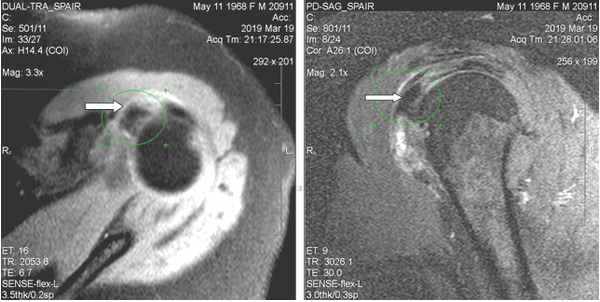

При магнитно-резонансной томографии (март 2019 г.) выявлены неравномерный отек капсулы, неоднородная оссификация капсулы в медиальном отделе. В полости сустава физиологическое количество жидкости. В субдельтовидно-субакромиальной сумке небольшое количество выпота (толщиной до 0,2 см). Суставная щель равномерная, признаков подвывиха головки плечевой кости не выявлено. Краевые заострения суставной впадины лопатки. Акромиально-плечевой промежуток 0,7 см (достаточный). Умеренный отек околосуставных мягких тканей. Ротаторная манжета: сухожилие надостной мышцы с явлениями слабого отека, целостность сохранена; сухожилие подлопаточной мышцы с явлениями слабого отека и дегенеративных изменений; целостность остальных сухожилий (подостной, малой круглой мышц) не нарушена, структура сухожилий не изменена. По сравнению с МР исследованием от января 2018 г. отмечаются более раздробленная и обширная оссификация в медиальном отделе капсулы и субдельтовидной сумки; усиление отека околосуставных мягких тканей; основной кальцинат сместился кверху, под сухожилие надостной мышцы (ранее находился чуть дистальнее сухожилия подлопаточной мышцы) (рис. 2).

![]()

Рис. 2. МР-томограммы левого плечевого сустава пациентки Л., 50 лет (март 2019 г.). Определяется утолщение стенок субдельтовидной сумки, крупный кальцинат на 10-11 часах условного циферблата головки плечевой кости (обозначен стрелками), под сухожилием надостной мышцы. Обращают на себя внимание нечеткость контуров кальцината и перифокальный отек мягких тканей, что характерно для фазы резорбции и соответствует клинической картине

При компьютерной томографии выявлена диффузно-глыбчатая оссификация капсулы сустава по медиальной поверхности (на 8-12 часах условного циферблата головки плечевой кости по сагиттальным снимкам) на участке размерами 1,5х0,7х4,5 см плотностью от 200 до 890 HU (средней плотностью ~ 300 HU), медиальных отделов субдельтовидной сумки, в зоне малого бугорка (в области фиксации сухожилия подлопаточной мышцы), более «нежная» по капсуле вокруг вертикального сегмента сухожилия длинной головки бицепса; отсутствует в области фиксации остальных сухожилий ротаторной манжеты к большому бугорку и в самом сухожилии длинной головки бицепса (рис. 3). Данный характер оссификации также подтверждает представления о фазном характере течения рассматриваемой патологии.

Рис. 3. КТ левого плечевого сустава пациентки Л., 50 лет (март 2019 г.). Аксиальный срез (а) на уровне верхней части головки плечевой кости: бобовидной формы крупный кальцинат по медиальному контуру головки плечевой кости в зоне расположения капсулы; МПР-корональный срез демонстрирует расположение кальцинатов по капсуле вдоль вертикального сегмента сухожилия длинной головки бицепса (б), МПР-сагиттальный срез весьма наглядно показывает локализацию кальцинатов по капсуле и в зоне субдельтовидной сумки (в) и 3D реконструкция правого плечевого сустава в объемном представлении детализирует патологическое состояние в мягкотканых структурах сустава (г). Визуализируется оссификация капсулы вокруг сухожилия бицепса; кальцинаты в подклювовидном и субдельтовидном пространствах